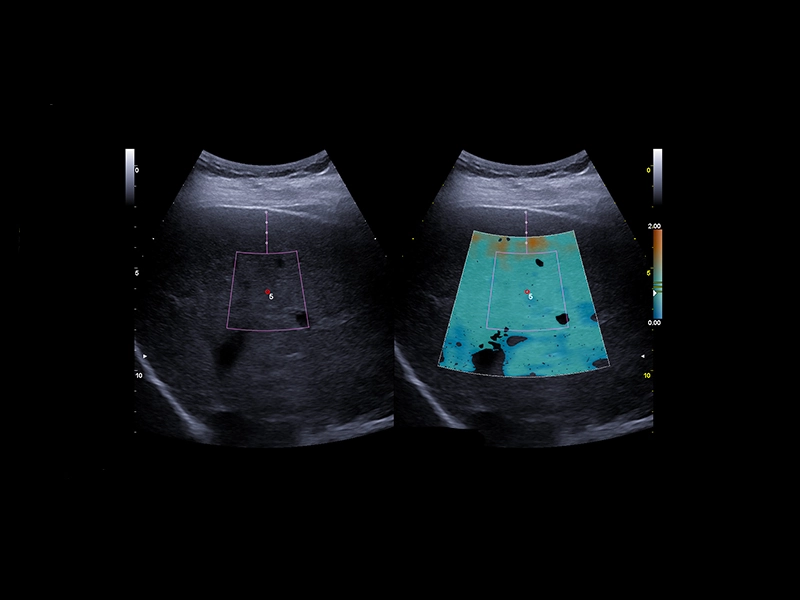

MyLab™C30 - QElaxto 2D liver

MyLab™C30 - QElaxto 2D liver

MyLab™E80 - QAI - Liver

MyLab™E80 - QAI - Liver

MyLab™9 Platform - QElaXto point Shearwave Elastography in liver

MyLab™9 Platform - QElaXto point Shearwave Elastography in liver

MyLab™9 Platform - QElaXto 2D shearwave elastography in liver

MyLab™9 Platform - QElaXto 2D shearwave elastography in liver